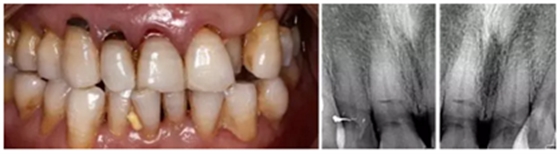

1.臨床病例:患者,男,年齡73歲,不慎摔倒至右上頜側(cè)切牙、左右上頜中切牙外傷根折,X線檢查:12、11、21折裂線達(dá)牙頸部以下。CBCT檢查:12、11、21折裂線呈水平狀,達(dá)牙頸部以下。

2.診斷:左上頜側(cè)切牙、左右上頜中切牙根折